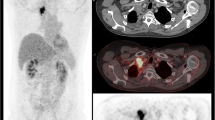

Initially, the metabolic changes over time in patients with relapsed or refractory HL undergoing anti-PD-1-treatment were described by Dercle et al. [56]. Subsequently, the same group demonstrated that a decrease of 18F-FDG-avidity in tumour and spleen as well as the general 18F-FDG-avid tumour burden 3 months after initiation of anti-PD-1-treatment were associated with improved clinical outcome [55]. Consequently, CT-based response evaluation had to be reclassified when additionally applying PET criteria in 44% of HL patients undergoing nivolumab. Among these, the majority showed complete metabolic response in contrast to CT (Fig. 1) with improved clinical outcome [57]. In the setting of early treatment response of HL and anti-PD-1-treatment, both Lugano criteria and LYRIC performed equally with equivocal findings [58], a result that possibly relates to the rather rare occurrence of pseudoprogression in HL [55, 56, 59].

With regard to PET/CT imaging in CAR-T cell therapy, only limited data is available. Firstly, Shah et al. [60] demonstrated in a small set of diffuse large B cell lymphoma and follicular lymphoma that patients with complete remission of the metabolic tumour volume on 18F-FDG PET 4 weeks after CAR-T cell therapy showed a long-term remission over 2 years and patients with remaining activity had an early relapse. Secondly, Wang et al. [61] showed that a higher 18F-FDG-avid tumour burden prior to therapy was associated with more severe CAR-T cell therapy-related side effects. Interestingly, this study also demonstrated that the phenomenon of pseudoprogression and local immune activation can also occur in patients undergoing CAR-T cell therapy (Fig. 2). Of note, several trials are underway evaluating the particular contribution of PET imaging in the course of CAR-T cell therapy (e.g., NCT03086954, NCT02476734).

A patient example with pseudoprogression of diffuse large B cell lymphoma undergoing chimeric antigen receptor T (CAR-T) cell therapy. Eight weeks after reinfusion of CAR-T cells, numerous abdominal lymph nodes with highly increased metabolism occurred, but fully resolved in the further disease course without additional treatment